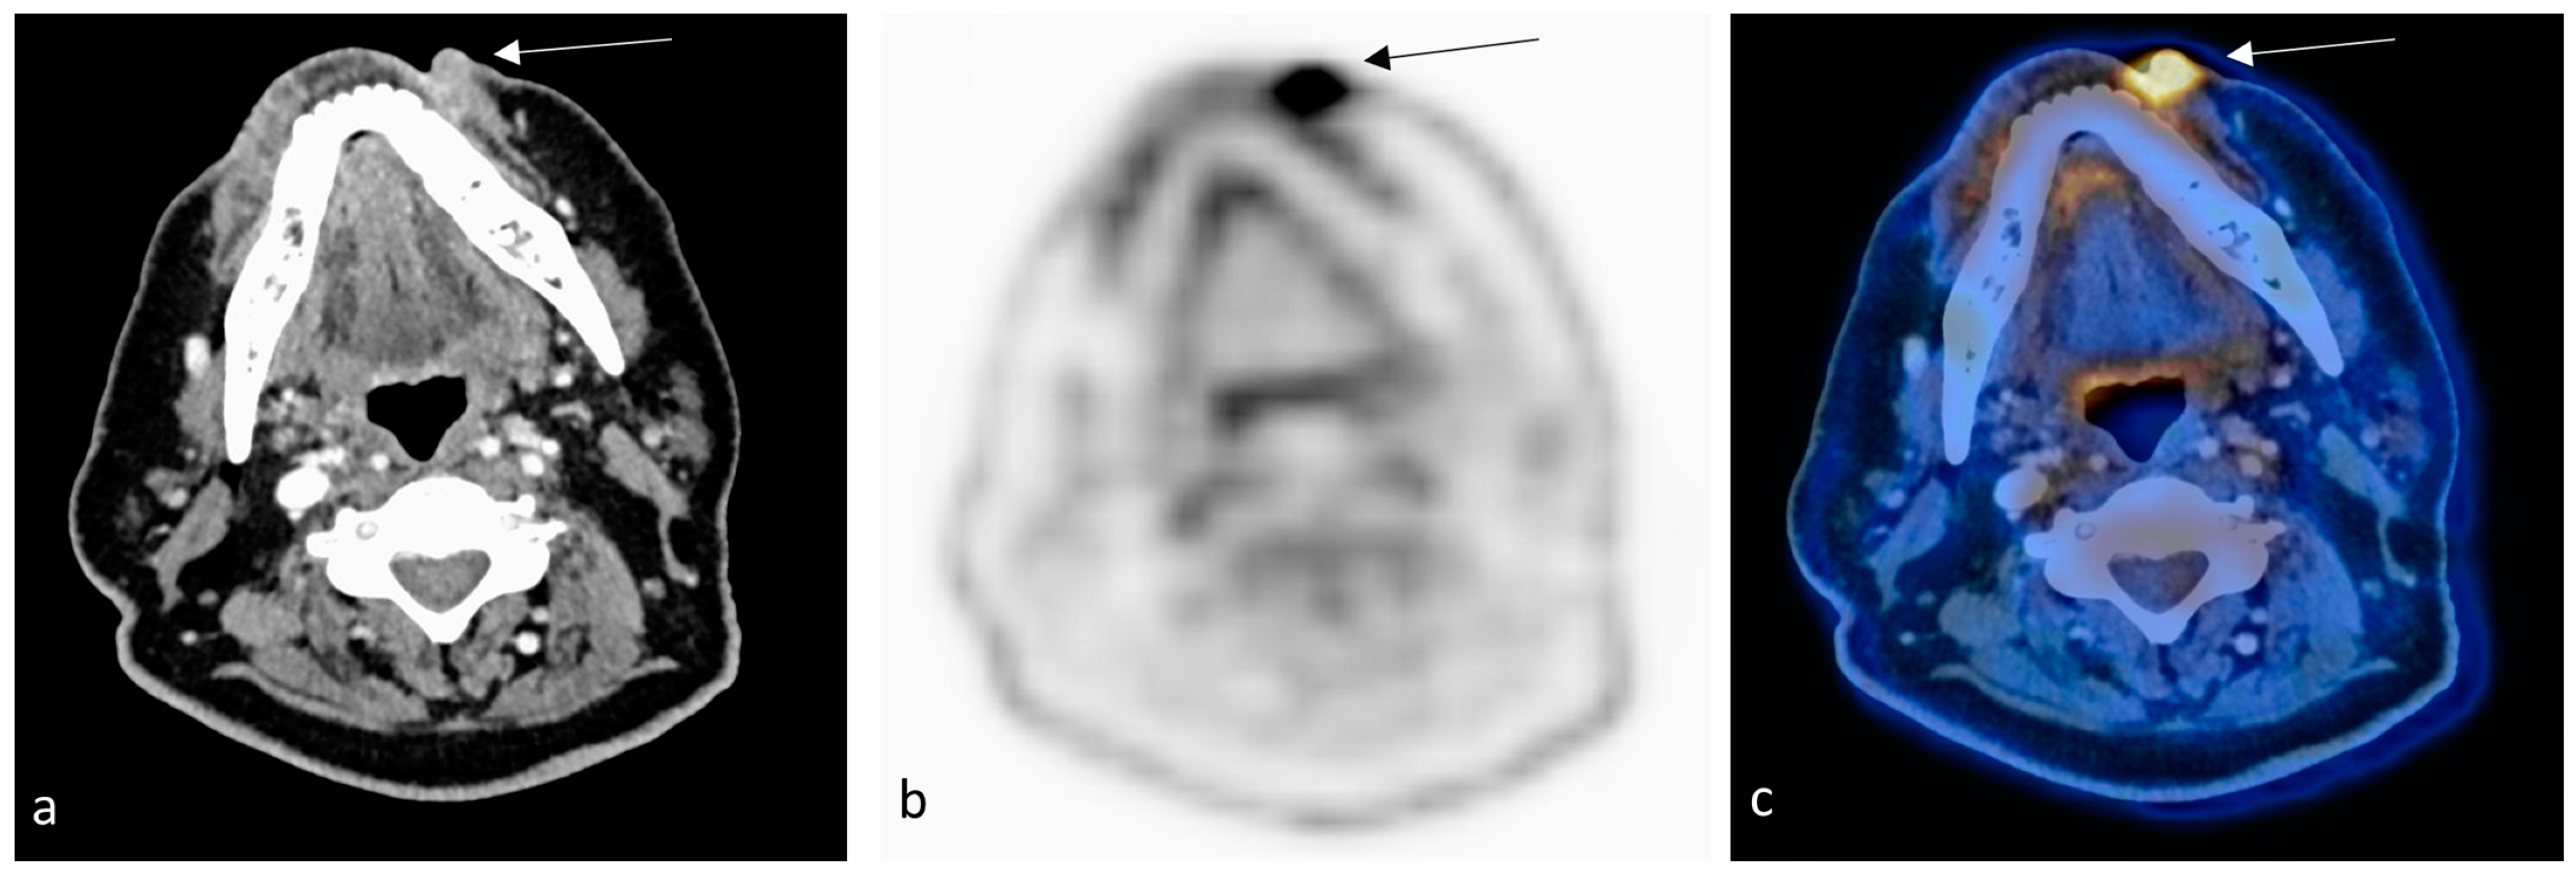

2. Case Report